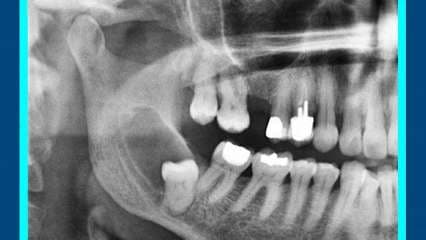

Las famosas cordales, o como las conocen algunos, muelas del juicio, son el motivo de molestia para muchos porque están asociadas a dolor de cabeza, inflamación y hasta desacomodo dental.

Para responder estas y otras preguntas, hoy nos acompañó el cirujano maxilofacial Daniel Rodríguez.